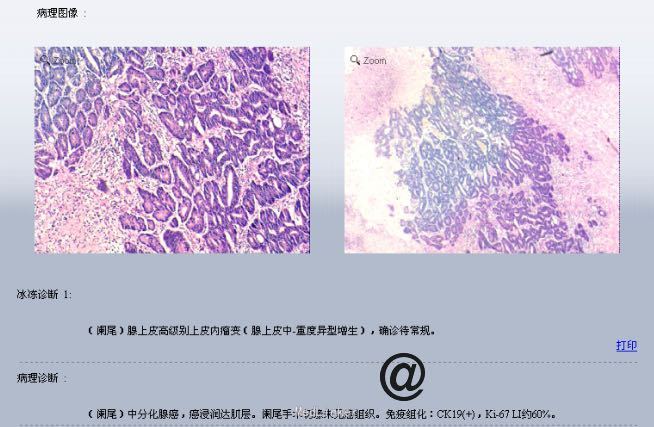

请妇科会诊,该科医师行妇检未见明显包块,且CA125正常,建议行小肠检查,同时行彩超探查了解包块来源,妇科彩超:子宫较小,宫体后壁肌壁间肌瘤(稍凸向宫腔),右侧附件区实质性包块,考虑为右侧卵巢肿瘤,左侧附件区未见明显异常显示,盆腔未见明显积液。 请妇科商议并于患者沟通后于2015.10.08转入妇科,转科行积极完善术前准备,于10.16行剖腹探查术。术中见:子宫稍大,质硬,后壁与直肠致密粘连,左侧卵巢大小正常,右侧卵巢增大直径约4cm,双侧附件与子宫后壁及盆壁致密粘连,分离盆腔粘连后可见巧克力样液体,阑尾可见约9*5*4cm肿瘤,包膜完整,与周围组织无粘连。请胃肠外科主任上台会诊,行阑尾切除术,术中快速病理切片检查示:(阑尾)腺上皮高级别上皮内瘤变(腺上皮中-重度异型增生),确诊待常规。再次向家属交代病情,将快切结果告知患者家属,患者家属了解病情,要求切除右半结肠,切除全子宫及双侧附件,最终行:全麻插管下行右半结肠根治性切除+肠粘连松解+腹式全子宫切除+双侧卵巢输卵管切除术。术后病检提示:(阑尾)中分化腺癌,癌浸润达肌层。阑尾手术切缘未见癌组织。免疫组化:CK19(+),Ki-67 LI约60%。子宫附件及右半结肠:1.送检肠管粘膜组织呈慢性炎,粘膜下水肿,纤维脂肪组织增生,血管扩张、充血。肠周触及淋巴结13枚呈反应性增生。 2.子宫腺肌症,囊性萎缩性子宫内膜组织,慢性子宫颈炎伴鳞状上皮化生。 3.(双侧)卵巢白体形成,(右侧)符合子宫内膜异位囊肿;(双侧)输卵管组织呈慢性炎,(右侧)伴系膜囊肿。